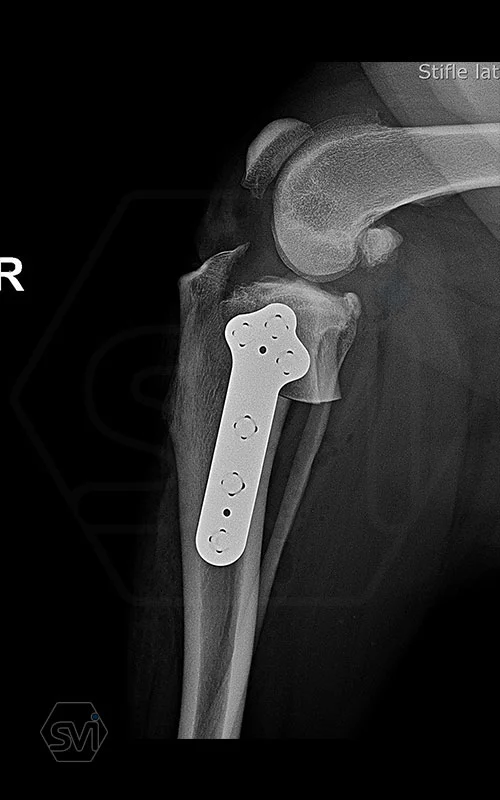

The NEW precontoured polyaxial locking TPLO plate family

One of the most important goals in the development of TPLO plates is, in addition to maximum stability, the simplest possible use, to facilitate the work of the surgeon, and to shorten the surgical time. Intraoperative modeling of plates often requires serious physical force, due to the deformation of the plate, weak points are formed in its material, which can lead to breakage of the plate or loss of lockig stability due to deformation of the holes. It can also lead to breakage of srews.

It is therefore advantageous to bend the plates in advance, conture them according to the anatomical shape, and then drill the holes. In most cases, the plates made in this way fit perfectly on the surface of the tibia, and the screws can be placed in the holes at the most optimal angle for maximum stability. Minor deviations in the fit of the plate to the bone surface do not need to be corrected for further intaraoperative curvature of the plate due to locking stability. And the polyaxiality allows you to choose the most optimal direction for inserting the screws.

The precontoured plates are designed so that using the monoaxial drill guide, all screws will be parallel to the plane of the tibial plateau, thus avoiding the screw being inserted into the joint and creating a screw-plate connection with maximum stability.